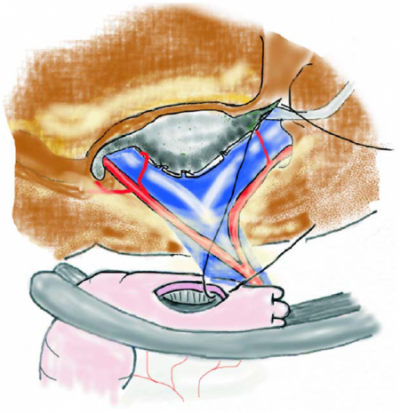

Texnika:

• Ümumi anestaziya altında aparılır

• Kəsik tərs L və ya sağ subkostal

• I mərhələ - III və IV seqmentlər arası sahənin açılması

• Ümumi öd axarının ekspozisiyası (hepatoduodenal bağın disseksiyası)

• Seqment III axarının identifikasiyası

• Bilioentral anastomozun qoyulması